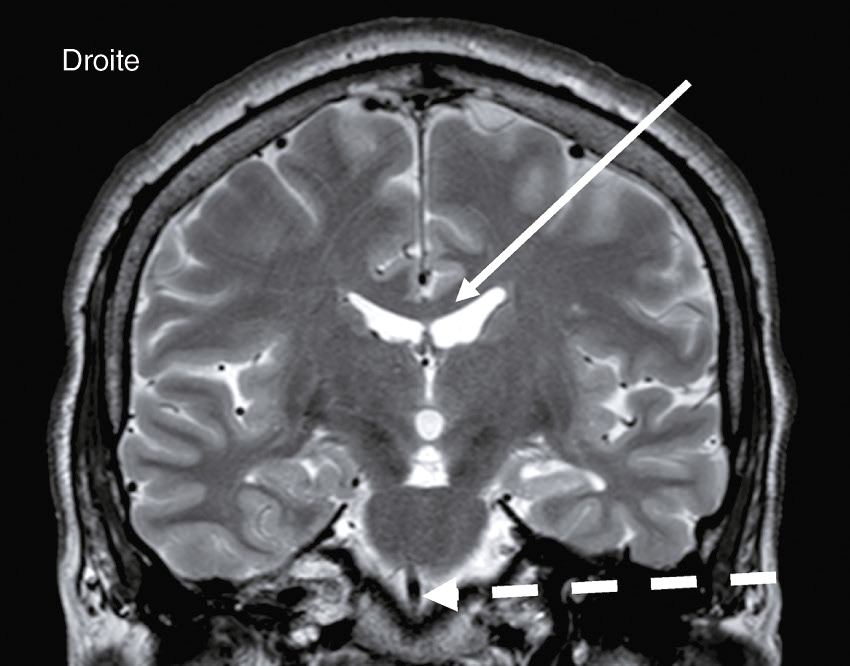

Devant cette atteinte du nerf III avec douleurs associées, vous souhaitez éliminer la présence d’un anévrisme carotidien, raison pour laquelle vous décidez de réaliser une IRM cérébrale avec ARM cervicale. Il n’y a pas d’anévrisme mais d’autres images attirent votre attention. Quelles sont les coupes et séquences utilisées pour ces deux images (fig. 31.12 et 31.13) ?

- A coupes axiales en séquence T2 injectées

- B coupes axiales en séquence T1 non injectées

- C coupes sagittales en séquence T2/FLAIR

- D coupes axiales en séquence T2/FLAIR

- E coupes axiales en séquence 3D TOF

Les lésions multiples visualisées sur cette IRM cérébrale (une ou plusieurs propositions exactes) :

- A concernent les territoires périventriculaires

- B sont en hyposignal T2/FLAIR

- C ne sont pas responsables d’un effet de masse

- D sont localisées dans la substance grise

- E sont localisées dans la substance blanche